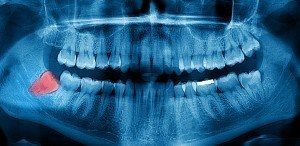

Why would we pull a tooth? Most of the time it is because it is impossible to restore the tooth at all, due to conditions like:

- Severe Gum Disease

- Extensive Decay

- Large Fractures

- Emergencies

- Trauma

- Infection

- Pain

When it is not possible to repair the tooth, we perform a tooth extraction it to prevent the infection from spreading to other areas inside of your mouth.